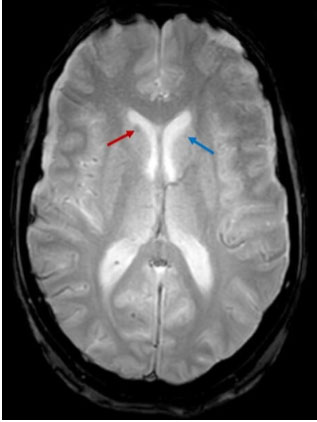

Brain MRI showed multiple nodular lesions in the frontal, parietal, occipital, and temporal lobes, in addition to the cerebellar hemispheres, not exceeding 2 cm in size, hyperintense on T1, hypointense on T2 and T2*, with nodular and ring-like enhancement after contrast (Figure 3, Figure 4, Figure 5), suggesting a melanomatous origin, in favor of a cerebral relapse of the anorectal melanoma.

Figure 4: An axial T2* MRI image showing two hypointense nodular lesions in the right (red arrow) and left (blue arrow) caudate nuclei.

On T2* WI: In 71% of patients, these lesions present whether a hyposignal on T2*, a hypersignal on T1, or both. Therefore, the association of T1 and T2* sequences can help suggest a melanomatous origin of intra-cranial lesions.